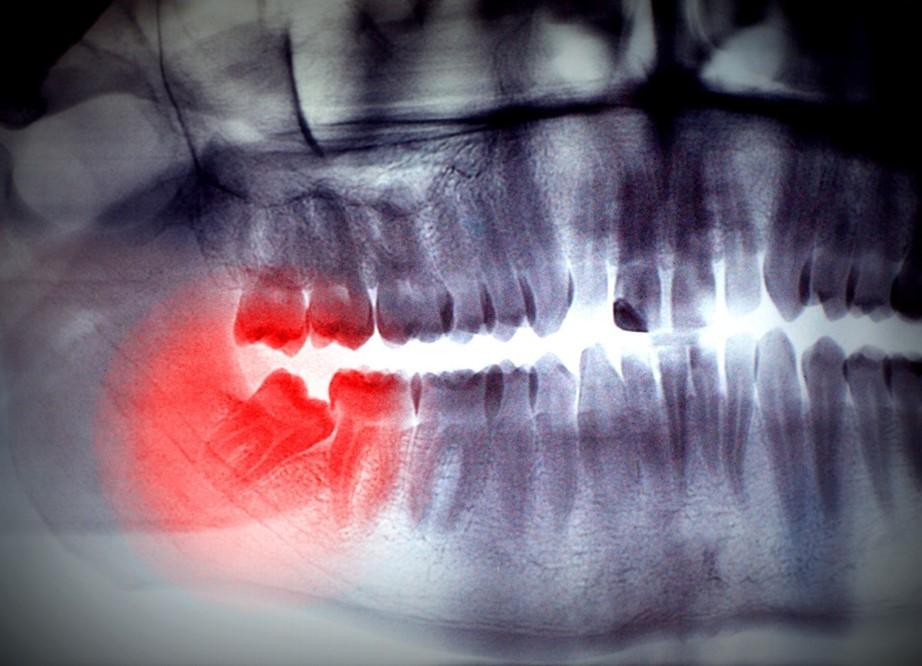

現時拔智慧齒前,專業的牙醫大多會安排照X光甚至電腦掃描評估好所有狀況才安排手術,所以拔智慧齒的風險已相對較低。

有些人拔智慧齒的風險特別高,是因為下排智慧齒比較接近面部三叉神經,拔除時可能會影響到神經系統的正常運作,因而引起下唇的輕微麻痺感。

有些病人的情況會慢慢回復正常,然而有些病人的情況卻是永久性的,所以拔除接近神經的智慧齒,最好由具豐富複雜手術經驗的口腔頜面外科專科醫生進行治療,以將風險減到最低。